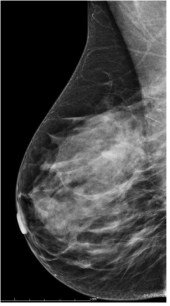

Qu’est ce que le MAMMOTEST ?

Mammographie de dépistage gratuite soit sur convocation soit sur prescription de votre médecin.